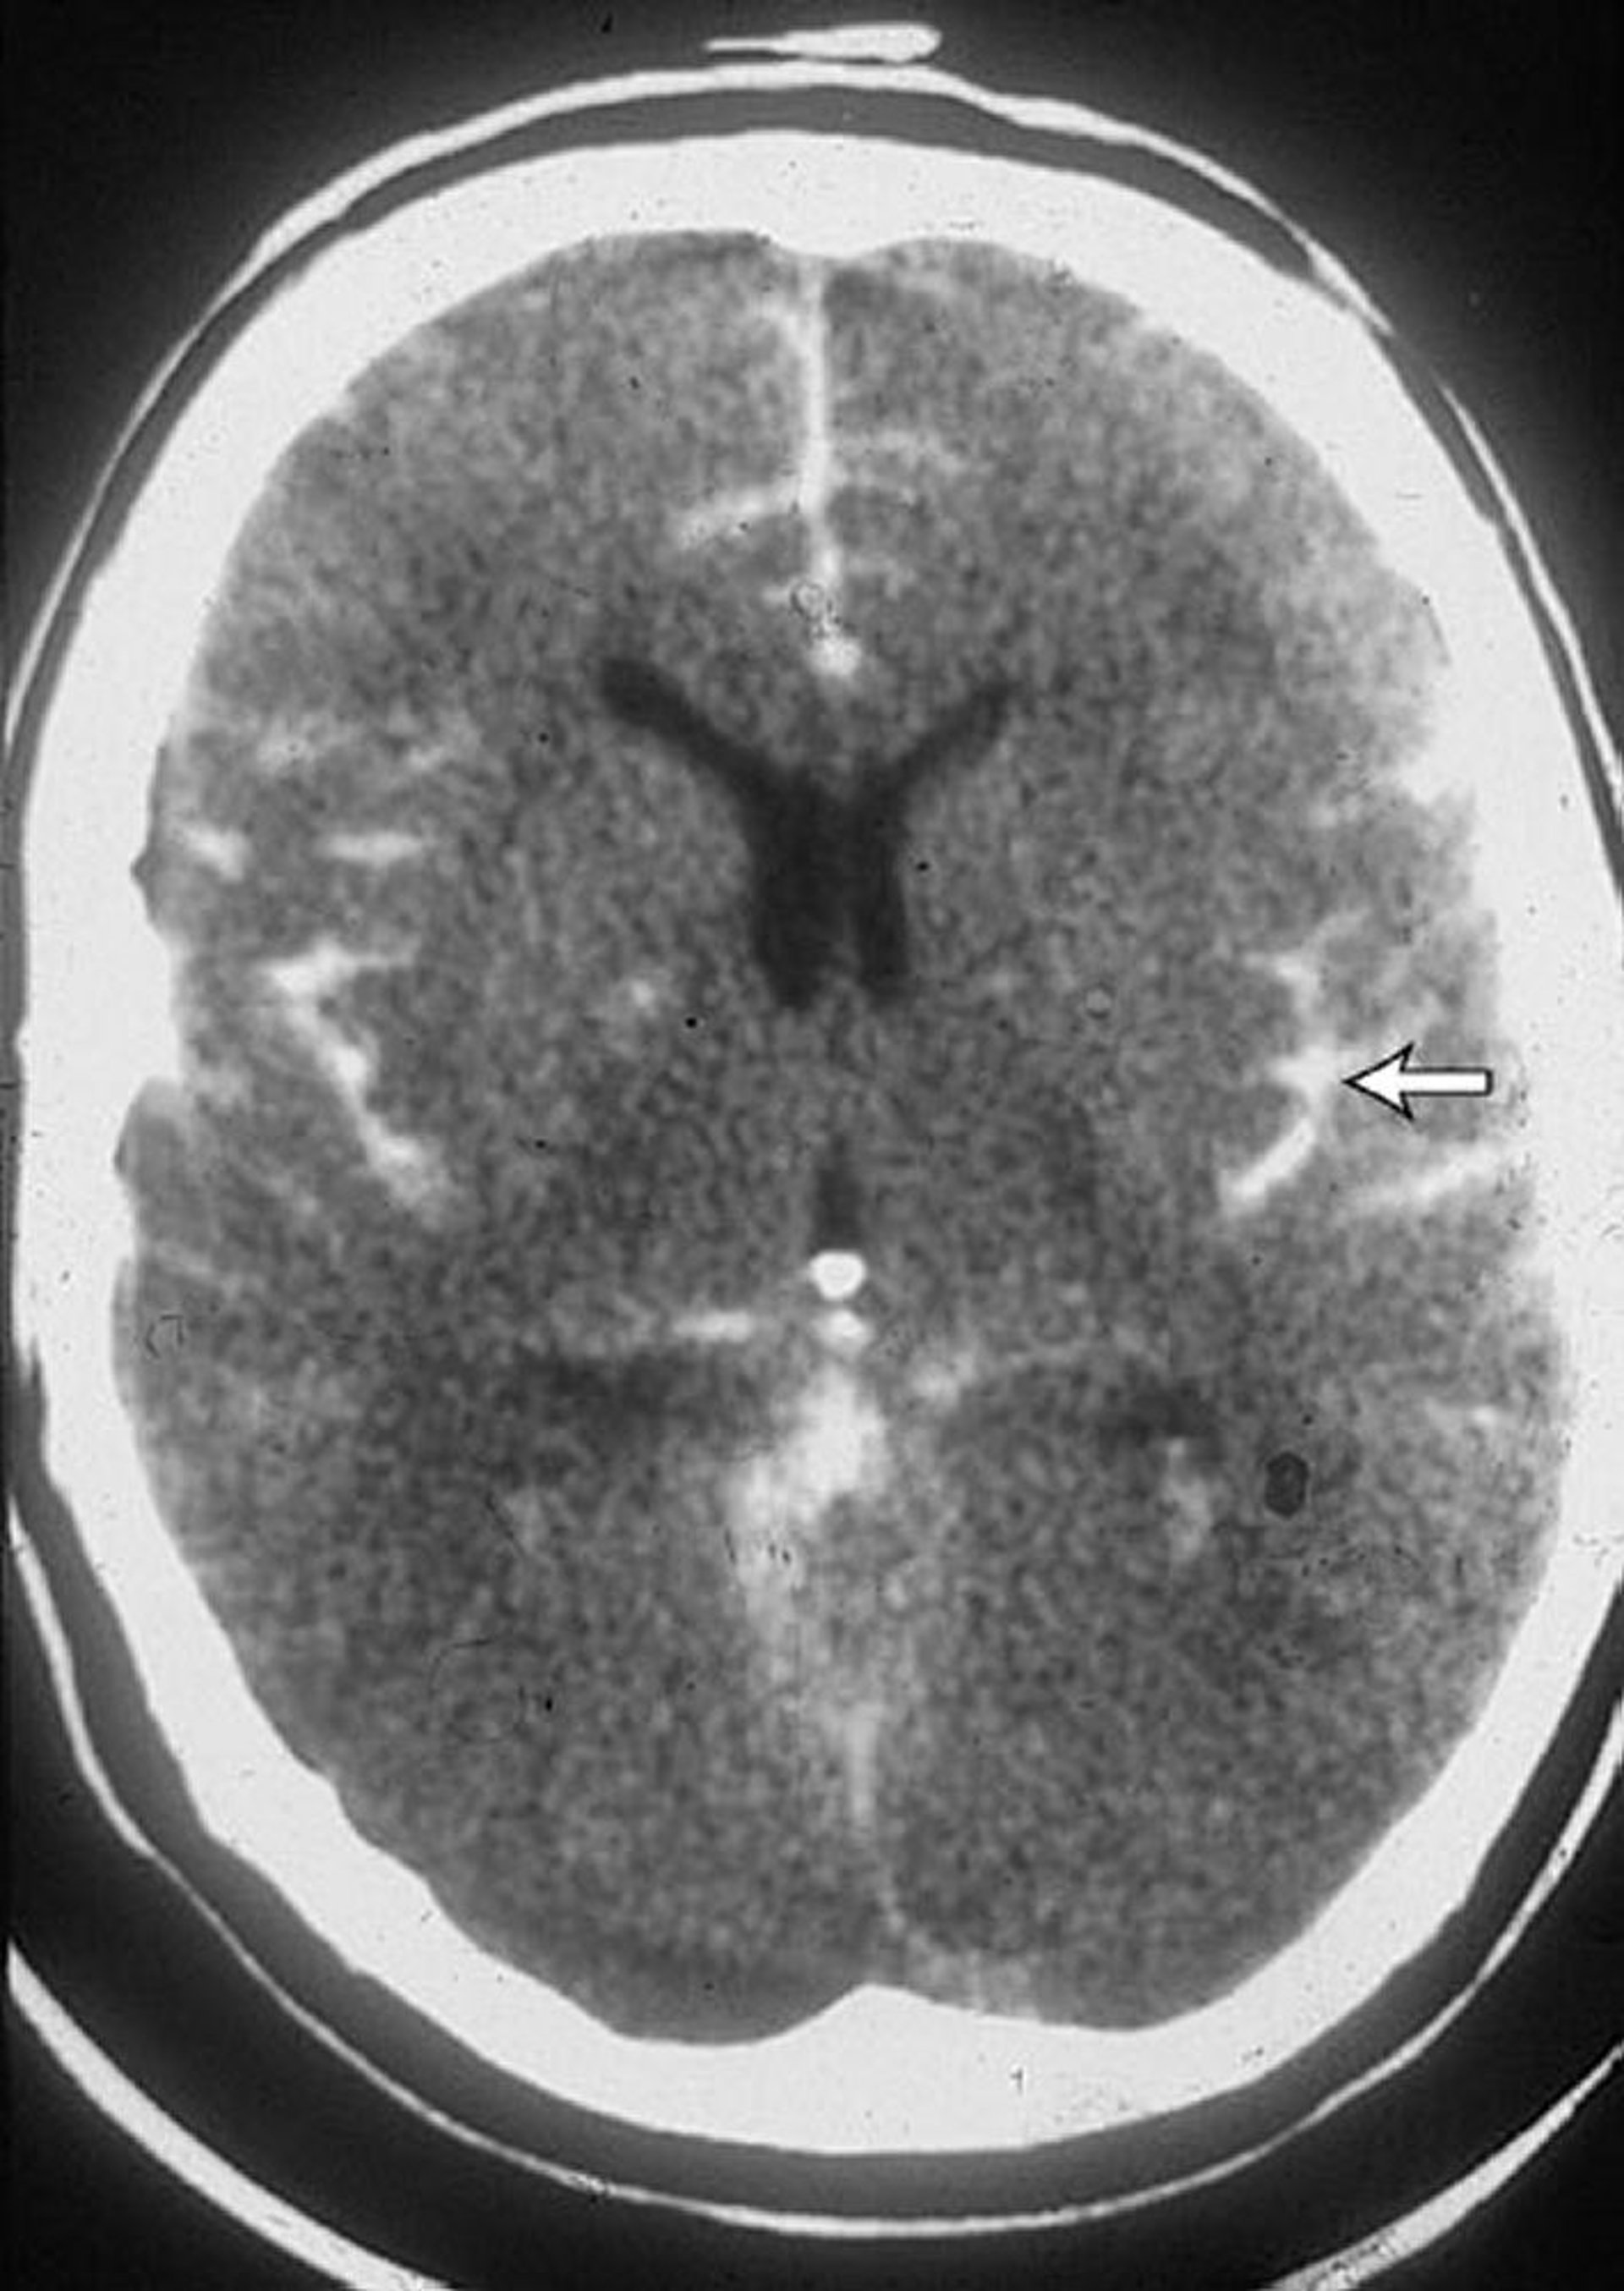

Hémorragie sous-arachnoïdienne

Cette TDM chez un patient qui a une hémorragie sous-arachnoïdienne montre du sang dans les scissures (flèche). Du sang est souvent également observé dans les ventricules.

By permission of the publisher. From Lenaerts M, Couch J. In Atlas of Clinical Neurology. Edited by RN Rosenberg. Philadelphia, Current Medicine, 2002.